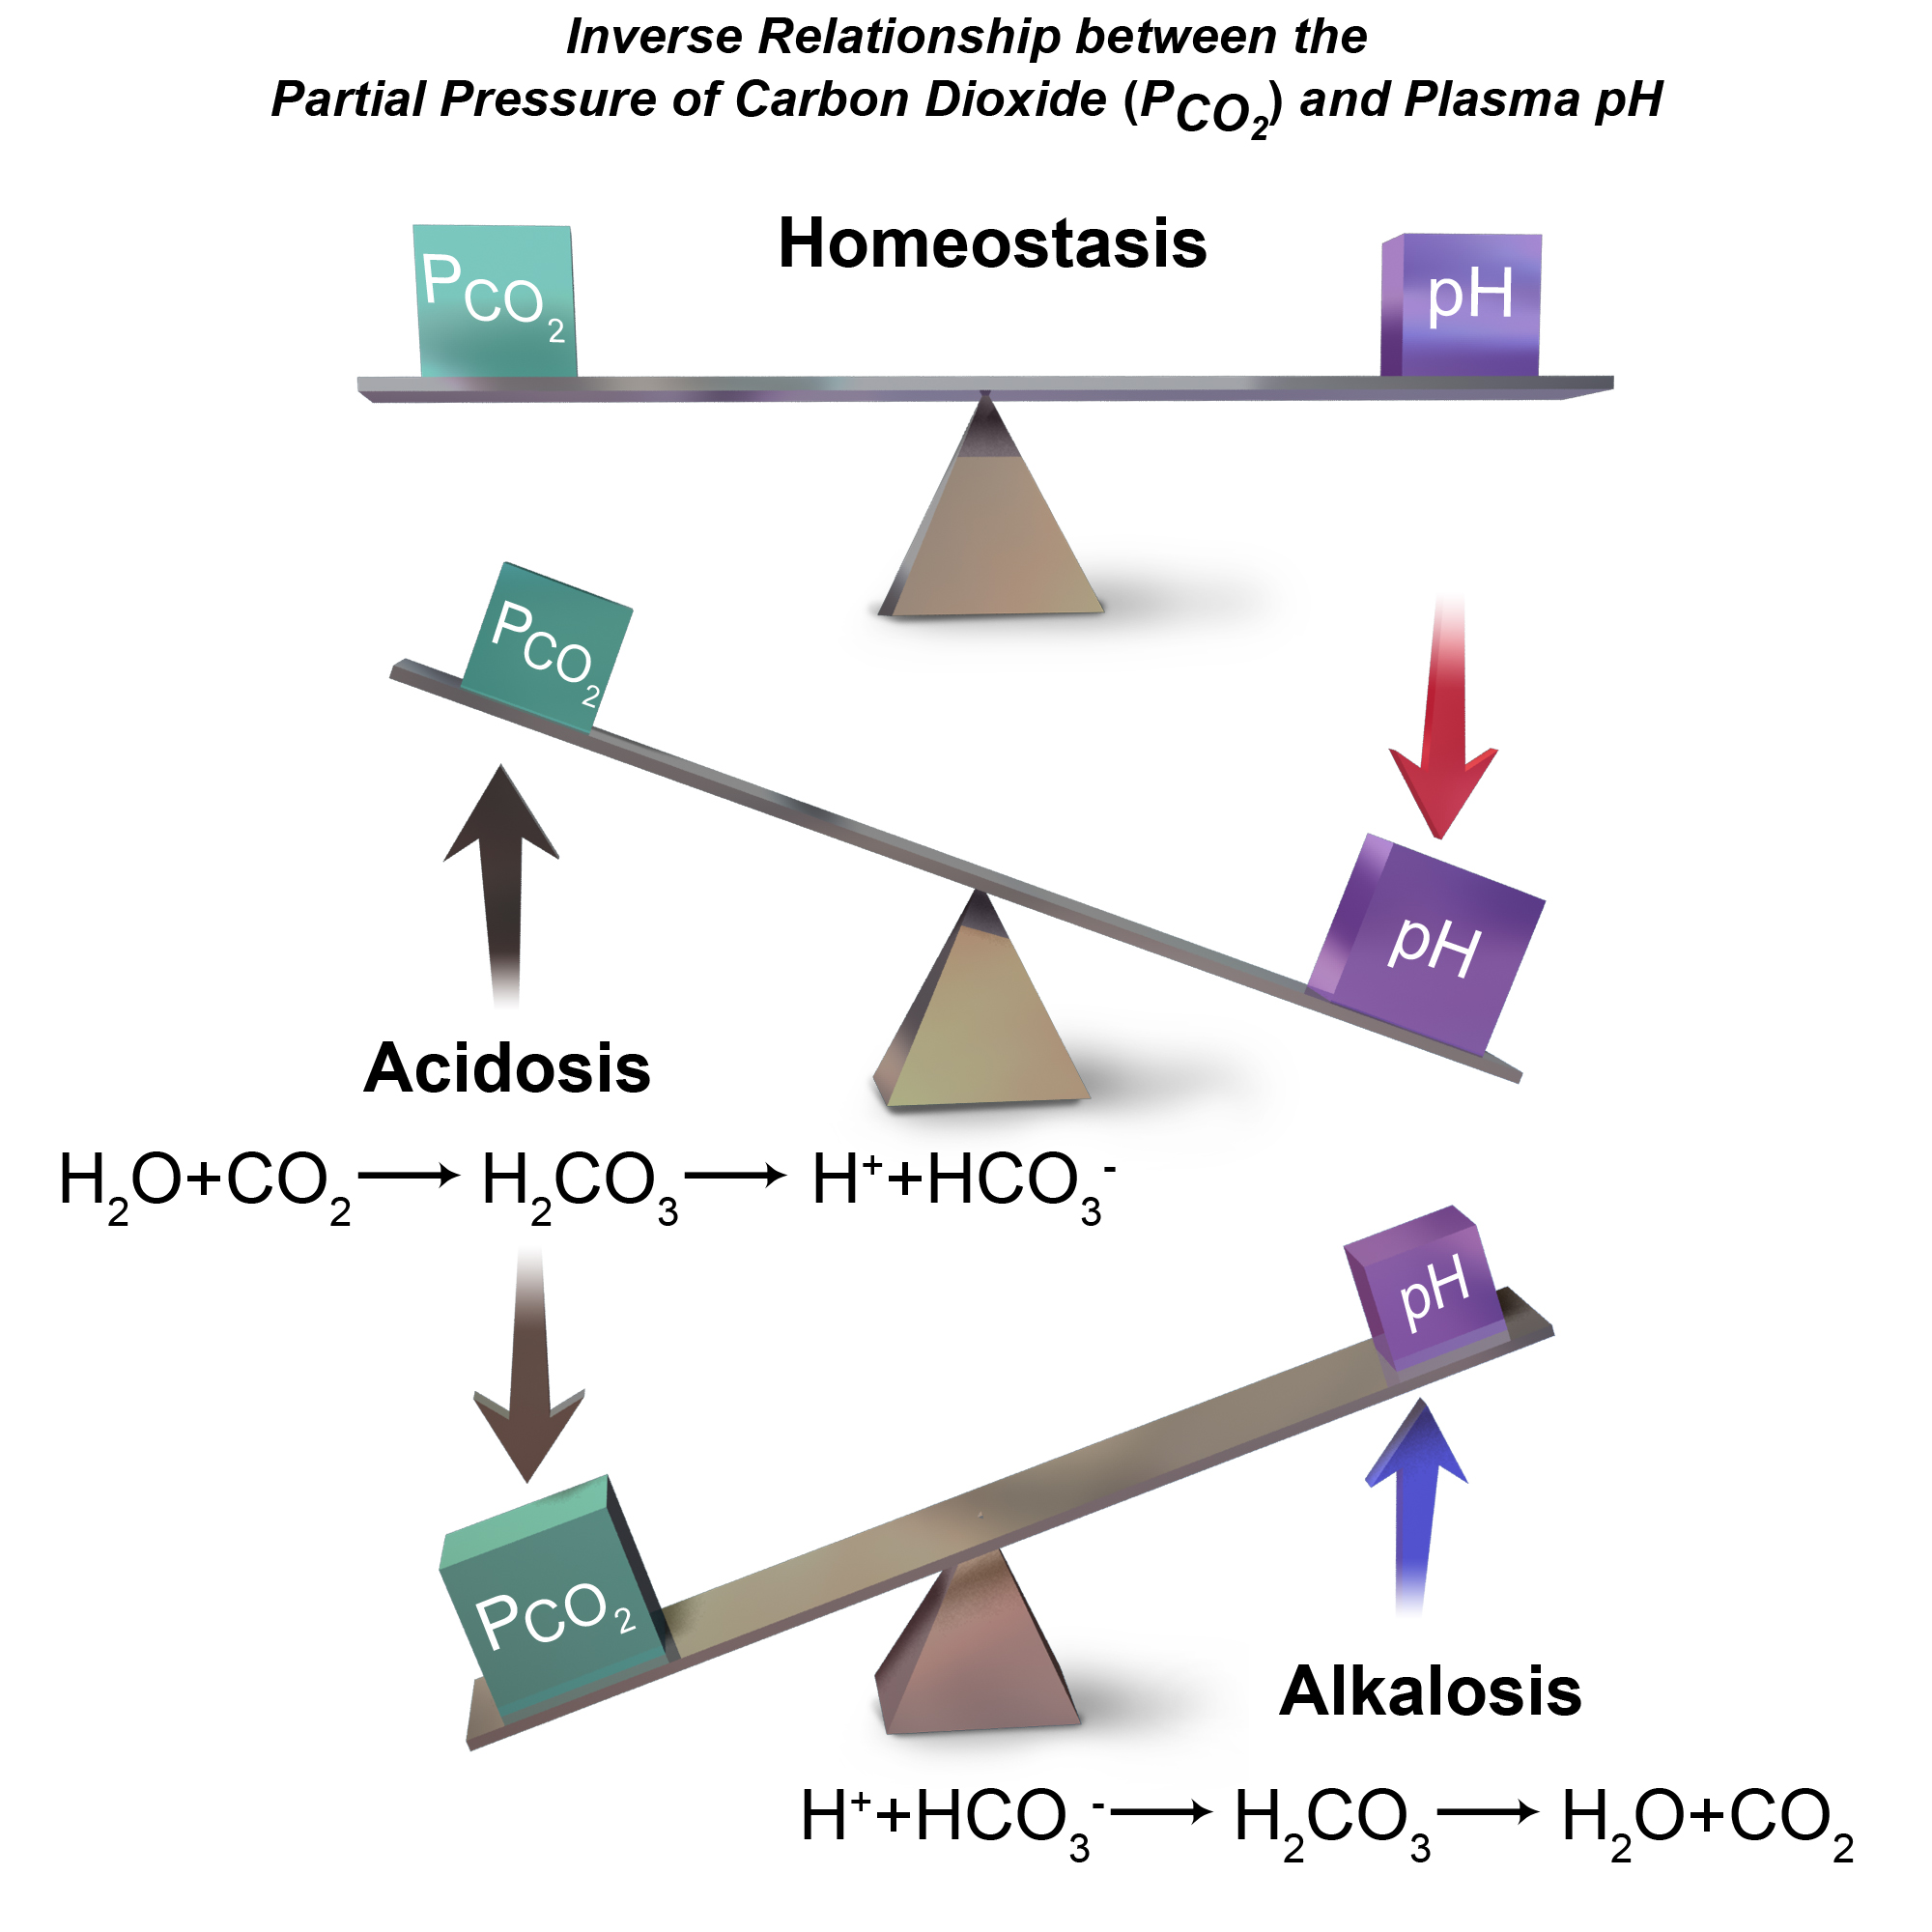

Hypercapnea – is also known as hypercarbia. It is a condition related to high carbon dioxide levels in the body. Carbon-dioxide can get built up in the blood if the body doesn’t successfully get rid of it within time. Conditions that either increase the levels of carbon-dioxide in the body or prevent the waste carbon-dioxide from getting to the lungs and discarded are usually the main causes of hypercapnea. Illnesses related to lung, brain, muscles and nerves are usually the most common causes. Hypercapnia is different to hypoxemia as hypercapnia is the condition with high carbon-dioxide levels in blood whereas hypoxemia is low oxygen levels in blood.

Respiratory failure is a critical condition that develops due to low blood-oxygen levels in the bloodstream that makes involuntary tasks like breathing almost impossible to do on your own. The low blood-oxygen levels results due to inadequate gas exchange during pulmonary circulation, which could be because of pump failure or lung failure. Pump failure is a ventilation failure which causes hypercapnia whereas lung failure is gas exchange failure causing hypoxemia. It can also de defined as arterial oxygen tension (Pao2 < 60mmHg) or arterial carbon dioxide tension (PaCO2).

Type II: – involves alveolar hypoventilation resulting in hypercapnia (PaCO2). There is a significant reduction in the alveolar minute ventilation that entails inadequate removal of carbon dioxide.

Acute respiratory failure vs chronic respiratory failure: In type II respiratory failures, there is active vs chronic respiratory failure, active failure matures and progress over minutes to a couple days and involves respiratory acidosis (a condition where lungs are not able to get rid of all the carbon dioxide in the body). On the contrary, chronic failure takes anywhere from days to months to develop and involves a higher PaCO2 including increased levels of serum bicarbonate due to renal compensation.